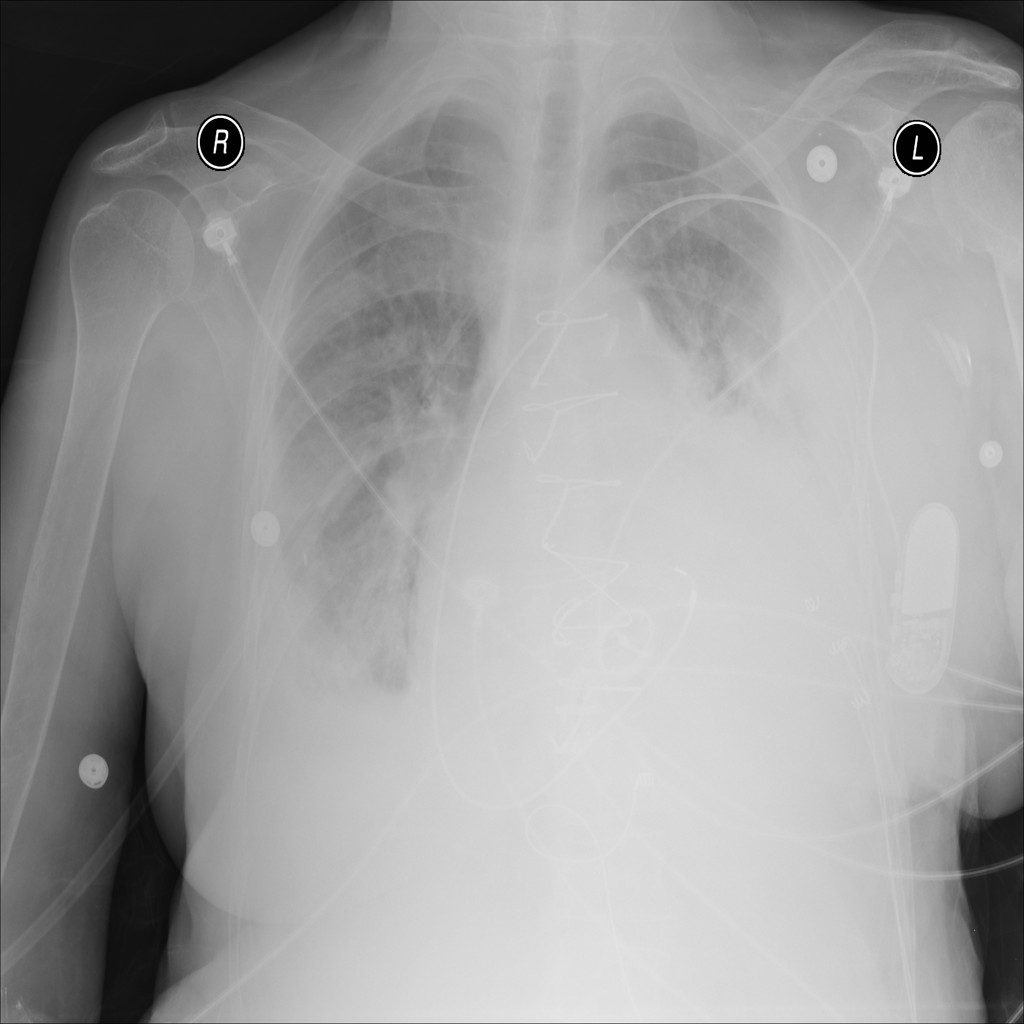

PAT-40F9 · IMG-004Effusion

PAT-40F9 · IMG-004

PA